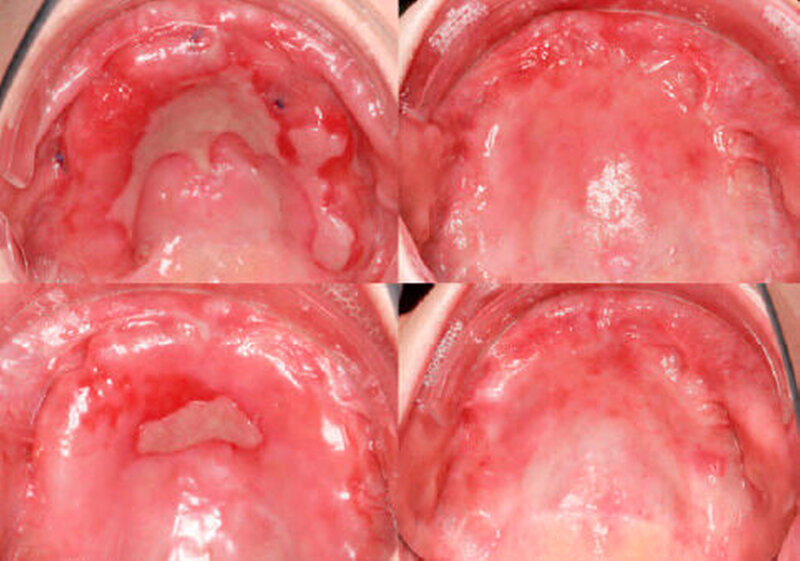

Anfang 2011 kam es erneut zu dunklen Veränderungen der Mundschleimhaut regio 11 bis 16 palatinal, die bioptisch abgeklärt wurden (Abbildung 4).

Histologisch ergab die Inzisionsbiopsie in regio 12 palatinal ein Melanoma in situ. Nach Aufklärung der Patientin erfolgte in Intubationsnarkose die komplette Entfernung der Gingiva fixa im Oberkiefer mit angrenzendem Alveolarknochen regio 12 palatinal sowie der Oberkieferrestbezahnung (Abbildung 5). In der gleichen Sitzung konnten durch eine Panendoskopie weitere maligne Veränderungen im oberen Aerodigestivtrakt ausgeschlossen werden.